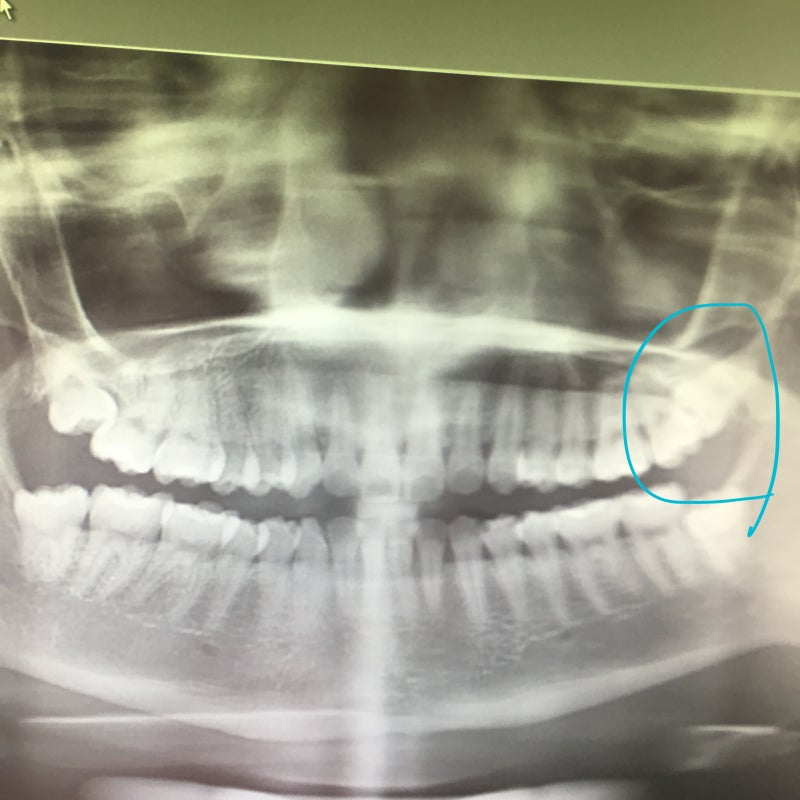

스마일라식 후기에 이어 사랑니발치 후기를 가지고 왔는데 수술이고 너무 고통스러워서 자세히 적어봅니다.<寻找智齿>내가 뭘 잘못했어? .?4 개요… ? 하나가 아니라 넷.. 더 무서운건 그 다음 2개의 치아는 매복 사랑니, 오른쪽은 비스듬히, 왼쪽은 눕혀져있는데 할건지 말건지 결정해보라고 하더라구요. 진행 상황을 볼 수 있습니다. 정상적인 사랑니가 잘 자라는 한 발치할 필요가 없다고 합니다. . . .

<大约10个月后> 약 10개월 후….. 나는 반복되는 치통에서 겨우 살아남았고 마침내 무언가가 시작되는 줄 알았다. 이것은 심각한 치통입니다. 몸이 안좋고 좋은 음식도 못먹고 예민합니다. 치통을 경험한 사람들은 공감할 것이다. 자신도 모르게 어금니처럼 보이고, 키가 좀 커서 사랑니가 아닌 어금니로 착각하기 쉽습니다. 하지만 1~2달을 기다릴 수 없어 사랑니 전문 병원을 찾아 예약을 하게 되었습니다. 빼기만 하면 되는 간단한 조작이라고 생각하시면 됩니다. 신경을 건드리면 심각한 일이 벌어질까 두렵습니다. 4분의 2도 기습을 당해 걱정을 금할 수 없었다. 수술 > 병월에 도착하여 간단한 검진을 받고 당일 수술을 받았습니다. 나는 모든 것을 제거하기로 결정했습니다. 먼저 같은 날 매몰 사랑니 1개와 정상 사랑니 1개 총 2개의 발치를 하기로 했습니다. 마취를 하는 순간 너무 무서웠다. 그렇게 아프진 않은데 잇몸에 바늘이 들어가는 것 같아서 정말 무서웠어요 ㅠㅠ 근데 너무 예민하셔서 그런 생각이 드네요. 너무 겁먹지 마세요. 저도 할 수 있고 여러분도 할 수 있습니다. 거의 못느꼈는데 선생님이 바로 나오셔서 빠지는건지도 몰랐네요 뽑았을때는 빠지지않고 제 얼굴이 뒤따랐다, 뿌리가 뽑히는 그 느낌. . . . 화분에서 식물을 뽑는 느낌.. .. 정말 지금까지 겪어본 통증 중 가장 고통스러웠어요. 진짜. . . . 이것이 최악의 고통입니다.